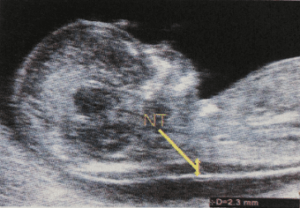

NT是一种观察后颈部皮下水肿厚度的检查。它存在于所有的胎儿中,即使NT很厚,仅凭这种检查也不能说明胎儿是正常还是不正常。另外,NT的厚度也与胎儿的大小有关,所以准确测量胎儿头顶的长度也很重要。

NT是在妊娠初期的有限时期内(11周~13周)在胎儿身上发现的正常・异常情况。NT本身不是一种疾病,而是胎儿妊娠初期特有的一种生理变化。一开始可能会增厚,但往往随着周数的增加而变得不太明显或消失。即使观察到NT增厚,也不一定是染色体疾病,而是可能潜藏有先天性心脏、骨骼或其他疾病。另外,不仅是NT,还可结合进行鼻骨・三尖瓣血流・静脉管血流等检查。

据说小于3.5mm。根据基准值准确测量,即使NT为6mm,也有50%的机会生出健康的宝宝。

胎儿超声波标志物检查

在中段截面扩大上半身以测量NT。